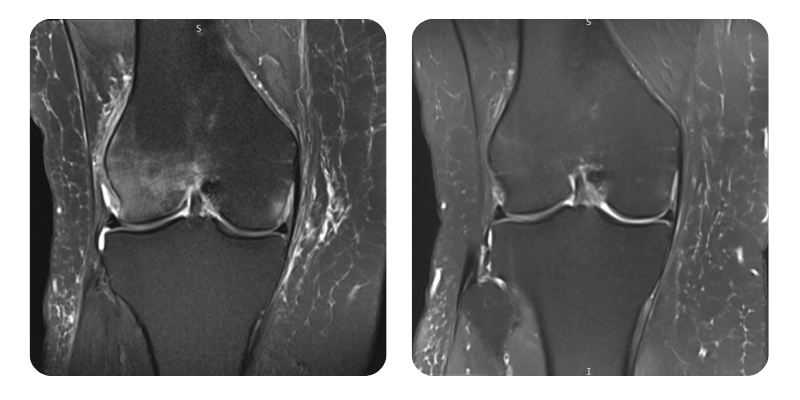

Prima

Dopo

S.M.S., 58 anni - Necrosi/edema del condilo femorale esterno destro

Diagnosi: Necrosi/edema del condilo femorale esterno destro; post fibrillazione atriale con ablazione, attuale ritmo sinusale; ipertensione arteriosa; diverticolosi.

Evoluzione: Si osserva una riduzione dell'edema all'RMN di circa il 90%.